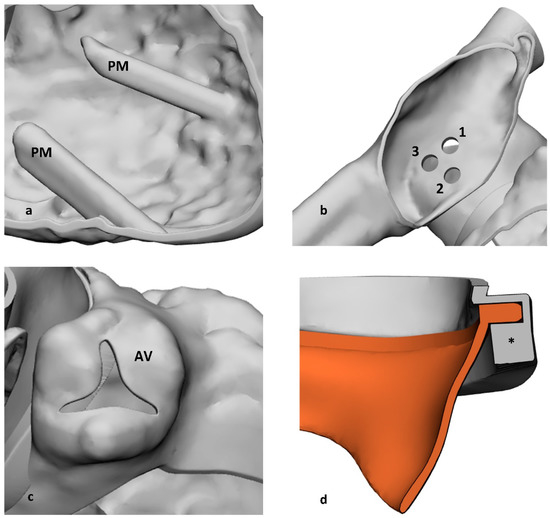

2.2. Computed-Assisted Design Modifications

2.2.1. Additional Anatomical Features

2.2.2. Adaptation of the Model to MCP

2.2.3. System Modularity